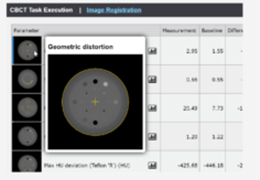

ANYTHINK 经导管主动脉瓣膜置换术分析系统